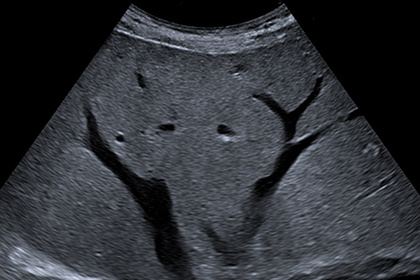

Почему на УЗИ видны огромные сосуды

😀И к этой изменённой ткани, состоящей из наших мутирующих клеток, подходит сосуд. Кровь в нём сталкивается с препятствием в окружающих тканях и застрявшей в венах кровью.

Вследствие чего приводящая артерия расширяется и становится размером с палец.

Представьте, что на резиновый шланг, по которому течёт вода, кто-то наступил.

Что с ним произойдёт? - В месте затора резина начнёт увеличиваться в размерах.

Вот почему такие огромные сосуды наблюдаются по УЗИ в местах расположения миом и кист!